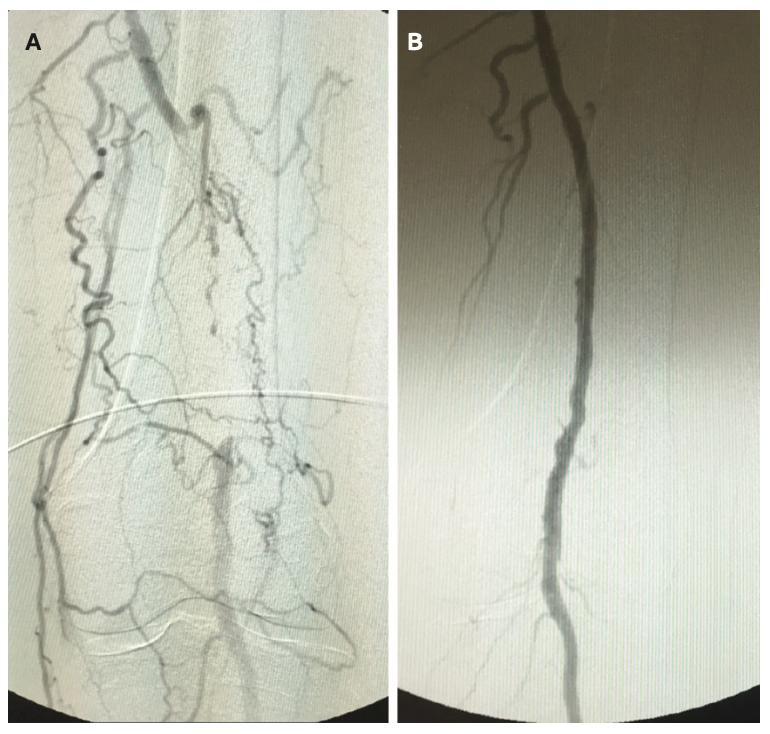

Once a patient presents with CLI, options of care are limited to amputation, peripheral vascular intervention (PVI), or a combination of both. Bypass may also be a consideration, dependent on the extent of blockage in the distal arteries, but often, once a patient presents with CLI, the disease state has progressed beyond the point of bypass being an option. Although there are risk factors with each treatment option, amputation carries a higher level of risk given the possibility of complications from an invasive surgical procedure, deep sedation, and the trauma of losing a limb. For below-the-knee amputations (BKA), a 2023 analysis by Beeson et al reported mortality rates of 4.18% at 30 days, 7.50% at 90 days, 10.88% at 1 year, and 16.67% at 5 years.3 Above-the-knee amputation (AKA) carries a higher risk of mortality, with rates at 9.27% at 30 days, 14.73% at 90 days, 19.40% at 1 year, and 24.49% at 5 years (Figure 1).3 Lower limb amputation has a significant impact on quality of life, as it not only affects the patient’s socioeconomic status and impairs mobility, but also has a systemic effect on the entire body. Patients can experience phantom limb pain, muscle contractures, fatigue, psychological issues with confidence and self-esteem, and have an increased fall risk due to changes in their center of gravity.

Once a patient is diagnosed with PVD, treatment options depend on the progression of the disease and may begin with medical therapies, including blood pressure control and statins, and smoking cessation. For advanced disease, options include surgical revascularization (bypass), peripheral vascular intervention, amputation, or a combination of these treatments. Treatment with 2 or more statins that includes aspirin and/or angiotensin-converting enzyme inhibitors/angiotensin receptor blockers (ACEi/ARB) is linked to a 65% reduced risk of mortality and a reduction in the risk of major adverse limb events.1 Although dual antiplatelet therapy is recommended post peripheral vascular intervention for 1 month and followed up with a lifetime platelet aggregation inhibitor such as clopidogrel, the phase 3 VOYAGER PAD trial has provided evidence that it is beneficial to add rivaroxaban, due to its ability to reduce the occurrence of thrombotic events. Including rivaroxaban in combination with aspirin early on in the pharmacological treatment resulted in a 15% reduction in major adverse events such as major bleeding, cardiac event, stroke, amputation, and mortality.5,6